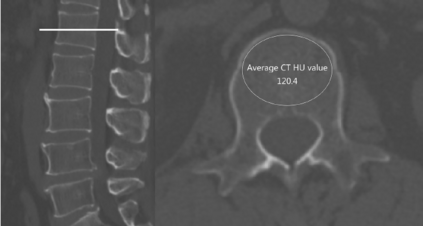

This work proposes a framework for the patient-specific characterization of the spine, which integrates information on the tissues with geometric information on the spine morphology. Key elements are the extraction of 3D patient-specific models of each vertebra and the intervertebral space from 3D CT images, the segmentation of each vertebra in its three functional regions, and the analysis of the tissue condition in the functional regions based on geometrical parameters. The localization of anomalies obtained in the results and the proposed visualization support the applicability of our tool for quantitative and visual evaluation of possible damages, for surgery planning, and early diagnosis or follow-up studies. Finally, we discuss the main properties of the proposed framework in terms of characterisation of the morphology and pathology of the spine on benchmarks of the spine district.